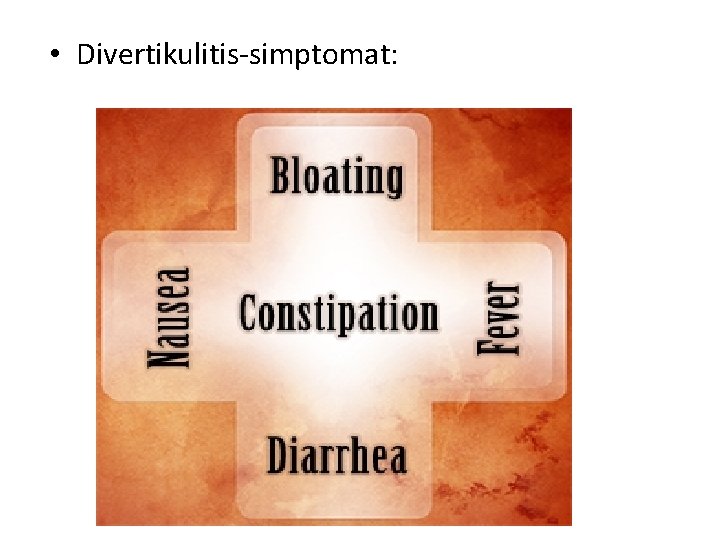

• Divertikulitis-simptomat: